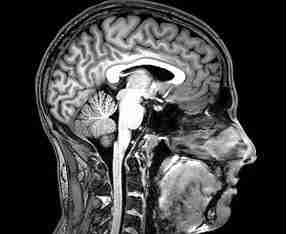

PHOTO COURTESY OF WIKIMEDIA

Democratic Rep. David Cicilline played Pop Warner football in his youth. Chronic Traumatic Encephalopathy has been detected after death in more than 200 men and boys who played football at the youth, collegiate and professional level.

The panel included researchers from Boston University who found that of 111 NFL players whose families donated their brains to research, 110 showed CTE signs.